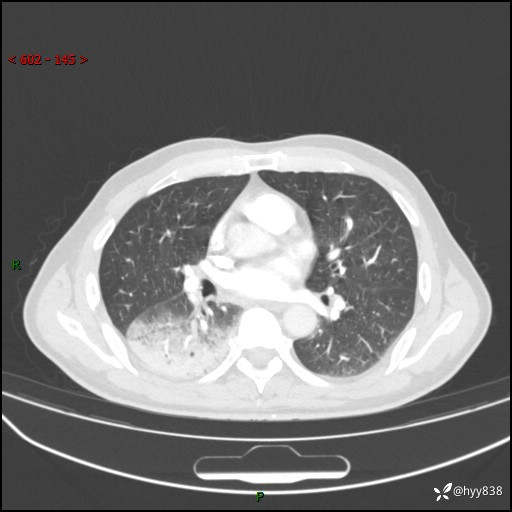

【患者信息】:63岁/男

【主诉】:发热5余天

【现病史及既往史】:患者5余天无明显诱因出现畏寒寒战发热,最高体温39.5℃,发热无明显昼夜规律,伴全身乏力、头晕,无头痛、无咳嗽咳痰、无胸痛咯血、无气短、无腹痛腹泻、无尿频尿急尿痛等不适,于当地市第五人民医院就诊,予以抗感染等治疗(具体不详)后发热无明显好转,1天前查胸部CT提示右下肺感染,为求进一步诊治,门诊以“社区获得性肺炎”收治入院; 起病以来,患者精神、食欲一般,睡眠可,大小便正常,体力体重较前无明显变化。

【检查】:胸部CT增强